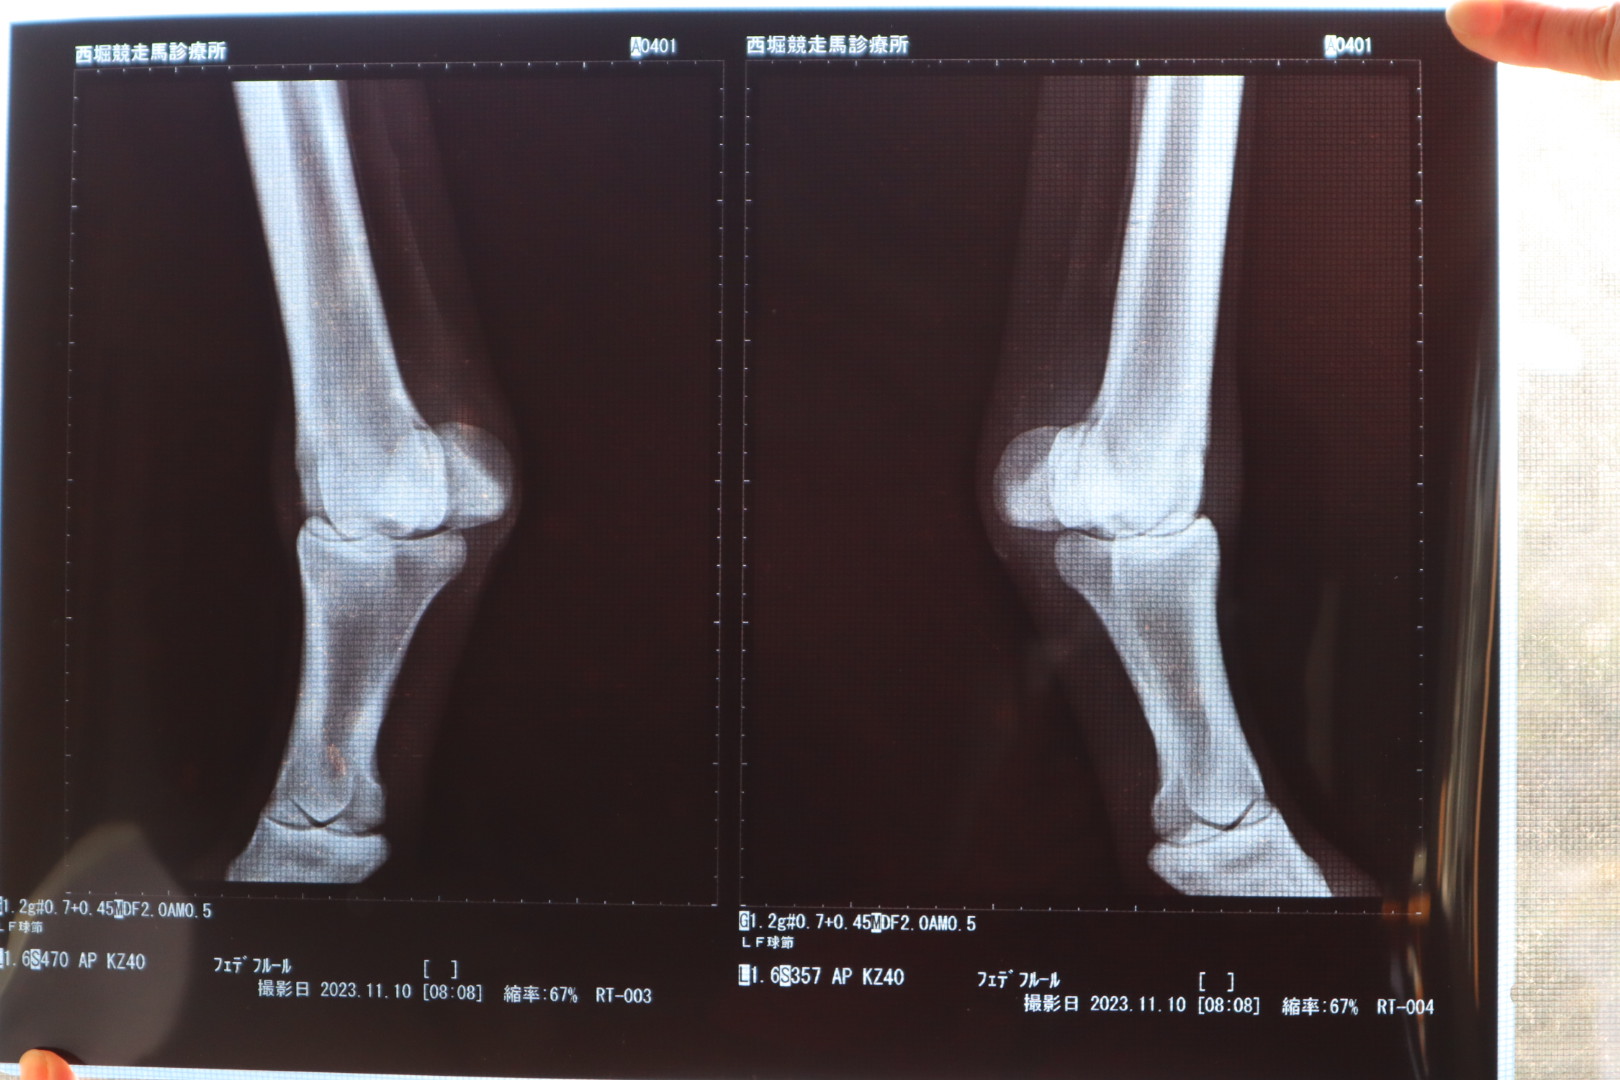

なお、オークション出品に伴い、2023年11月10日にレントゲン撮影を行ったところ、右前球節前面部に僅かに骨膜が確認されています。

※2022年3月8日(3歳時)調教後、軽度の跛行が見られたためレントゲン検査を行ったところ、右前第3中手骨にうっすらと骨折線が確認されました。事故見舞金12号(調教中の事故により事故発生の日から3ヵ月以上出走できなくなった場合)の適用を受けています。